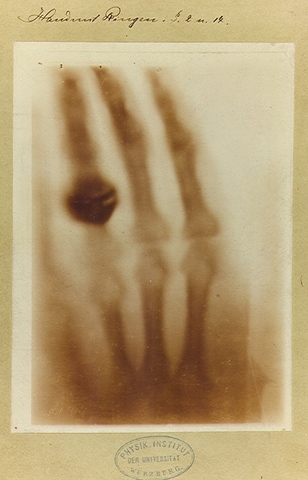

Roentgen realizó su primera demostración de los rayos X el 23 de enero de 1896 ante la Sociedad Médica Física de Wurzburg creando un fuerte impacto en los medios de comunicación y en la sociedad. Los hallazgos de Röntgen dieron lugar al desarrollo de toda una ciencia y de la práctica radiológica.

El descubrimiento y la introducción de rayos X en la práctica médica. Los experimentos de Roentgen, sus hallazgos y primeras conjeturas, y también las primeras experiencias prácticas en el campo de la Medicina. los primeros médicos que investigaron e introdujeron la evolución progresiva de la radiología gracias a figuras destacadas en este campo.